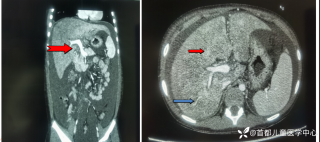

灼见|如果是你,如何处置山东男孩(多器官切除病例)

西地兰vip普外科医师

文/西地兰 特别声明:所有观点仅代表个人言论 特别声明:与当事双方均无利益相关 山东男孩,目前全网沸沸扬扬,看过一些观点,直言不讳地说,大多偏颇。要么一股脑地指责医方的全责,甚至有说千万别在县医院看病。要么又为医方无休止的遮羞,认为这样的手术在县医院做下来已经非常了不起。而我想到的是,以后面临类似的病例,我们怎么办?那么我们不如来一次专业的病案讨论。既然是事后讨论,难免有事后诸葛亮的感觉,但是假如下一次,同行们遭遇这样的病例,如何处置?这是医疗行业所面临的问题。希望我整理的这些思路和相关病例,对同行们有所帮助!就目前的资讯外界不足以判断是否需要急诊,如果需要急诊,那么只能根据术中所见进行处理,

目前知道的消息,第一,术前发现一个血肿,然后做增强CT发现一个占位,没说血肿与肿瘤的关系,术后病理没有描述肿瘤出现破裂出血,大概率就一个小血肿,我就不明白当地主任凭哪个指针去给这小孩开急诊刀的?哪个指南告诉他需要急诊开?第二,诊断不明确他想的不是进一步检查,一边观察一边进一步查,他反而选择腹腔镜探查,这个探查的指针在哪?第三,腹腔一个血肿,没有活动性出血,没有血压心率出现问题,为什么要开腹进去碰它?不能等血肿吸收再明确肿瘤性质吗?第四,1点进腹,3点病理结果出来,按这个时间还算顺利,应该还没出事,孩子还算平稳,病理是低度恶性,切了就治愈,他一年能开几台这手术,就敢继续做,拿孩子练手。第五,后面

2023年10月26日,来自山东菏泽市成武县的小烨和他家人的命运被彻底改变了。这个原本阳光、可爱的小男孩在一次意外被撞击后,在医院检查出了腹腔内存在肿瘤,并在手术中被切除了包括十二指肠、胰腺、大部分胃和小肠等多个器官。此后便无法再像正常人一样吃饭、喝水,活着要靠长期静脉注射营养液。一份2024年12月由第三方机构出具的司法鉴定意见书显示,当时给小烨做手术的成武县人民医院在该医疗行为中存在过错,与小烨的损害后果之间存在因果关系,建议医疗过错在损害后果中的原因力大小为同等原因。此外,另一份由成武县卫生健康局在2025年9月28日发出的书面答复中显示,成武县人民医院存在24小时内未完成病历;手术知情

豫刀匠秦 回复

医疗无小事,更何况牵涉到孩子,局部获益要让位于整体生存获益,SPT目前划为低度恶性,如果小于3cm可以局部切除,如果大于3cm,在主胰管附近,可以保十二指肠的胰头切除,当然保十二指肠还是要到大中心去,不过SPT应该也没有这么急切,不了解当时情况,无法置评,只能说术前评估有些草率了,当然有可能该县医院技术确实比较强,不过TPN,应该是损伤了SMA,或者SMV大出血缝闭了,不过SMV能修也能接,如果是SMB按理说不至于,只能说一句艺高人胆大!何况儿童手术,当慎之又慎!当下环境,窃以为病不好慎做,病人不好慎做,病人家属不好慎做!救命手术,下台为主!非救命手术,预后为首!炫技无用,又没人给你点赞加薪!